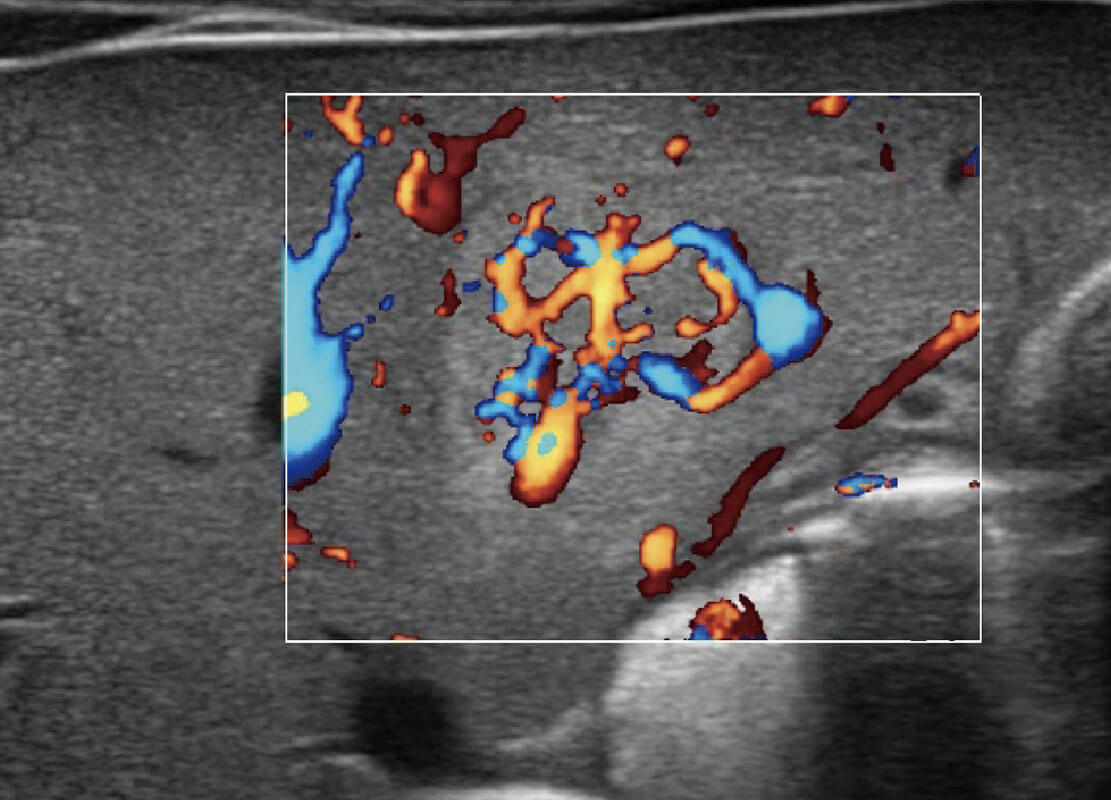

• 乳腺癌显微血流

• 新生儿肝血管癌